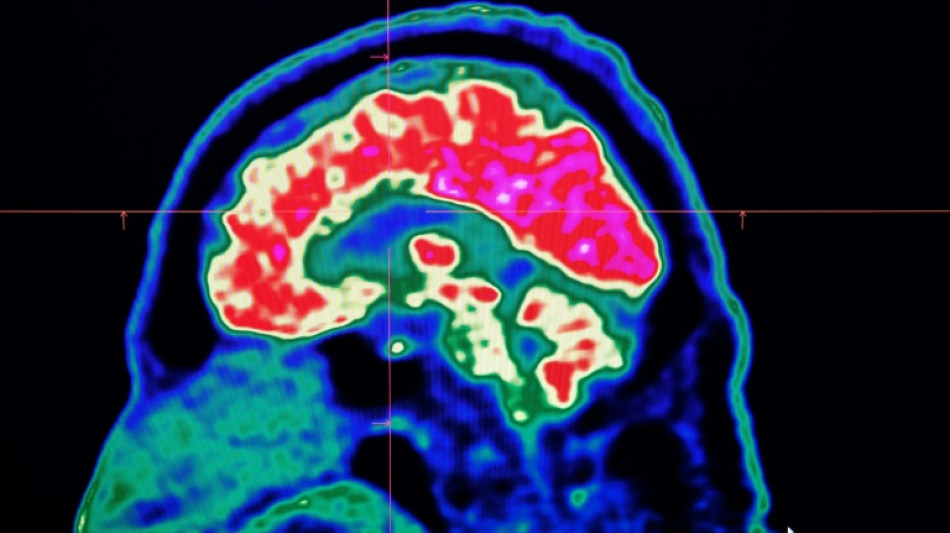

Surging nerve system disorders now top cause of illness: study / Photo: Fred TANNEAU - AFP/File

Conditions affecting the nervous system -- such as strokes, migraines and dementia -- have surged past heart disease to become the leading cause of ill health worldwide, a major new analysis said on Friday.

More than 3.4 billion people -- 43 percent of the global population -- experienced a neurological condition in 2021, far more than had previously been thought, the analysis found.